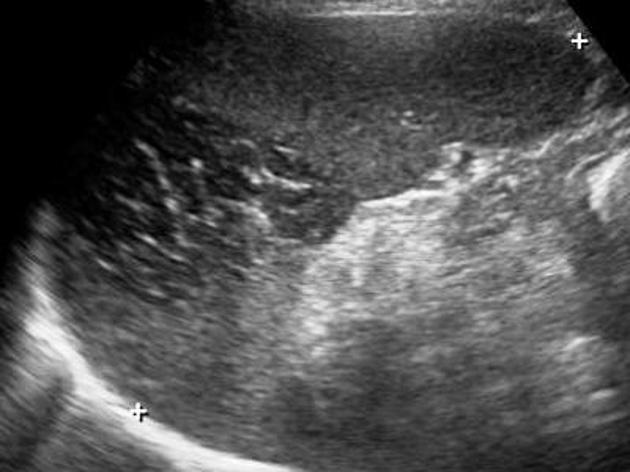

Echographie :

Echographie per cutanee ou echographie focalisee (

FAST ) de l'abdomen sont frequemment d'utilise dans

tous les cas infartus de la rate . Aspect echograhique est

image geographique ou triangulaire iso ou hypoechogene

a bord irregulier , mal limitee et a interieuse avait des

bands claire hyperechorich . Et sous echographie Doppler en

couleur . c'est une zone avascularisation .

Aspect

lesionnel d'une infartus de la rate est image en

plage ou en coin hypoechogene a bord irregulier avec

la base

oriente vers la capsule .Image echographique de la

rate en coupe longitudinal . |

Image ecdhographique d'une autre infartus

a pole inferieure de la rate avec aspect lesionnel

en plage hypoechogene a bord irregulier de mal

limite avec des band claire hyperechogene a

interieuse . Image echographique per cutanee en

coupe longitudinale |

Aspect lesionnel en

forme de coin hypoechogene avec sa base peripherique orrienter

vers le versant capsulaire . Sa bord est nette ,

irregulier avec des bands claires hyperechogene .

|